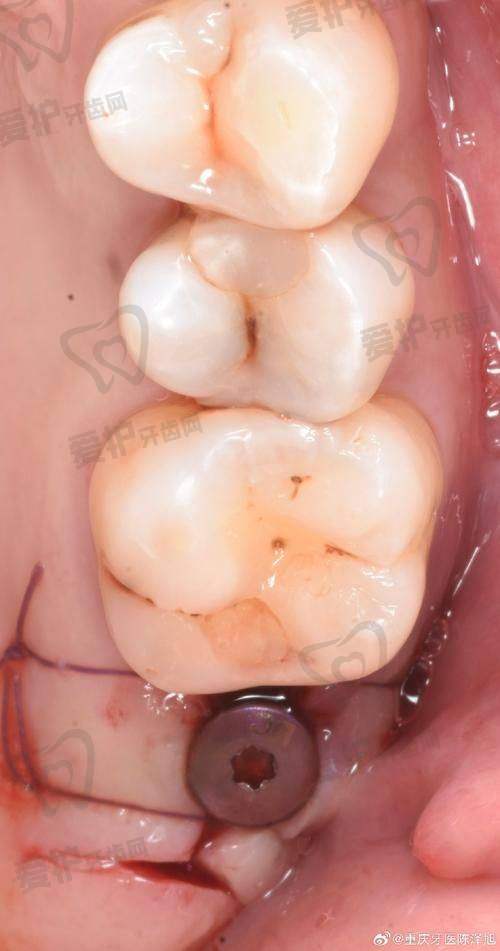

柳书喻医生擅长多种种植牙技术,如3D数字化种植技术、微创种植技术、水镭射种植技术以及即拔即种技术等。这些技术各有优势,能够满足不同患者的需求。

微创种植技术是柳书喻医生的拿手好戏之一。传统的种植牙手术创口较大,患者术后修复时间较长。而柳书喻医生的微创种植技术创口仅5mm,大大减少了对患者口腔组织的损伤。患者在术后疼痛较轻,修复速度也更快。

即拔即种技术是指在拔除患牙的同时立即植入种植体。这种技术可以缩短治疗周期,减少患者的痛苦。柳书喻医生在这方面也有丰富的经验,能够根据患者的具体情况判断是否适合采用即拔即种技术,并为患者提供相应的治疗方案。